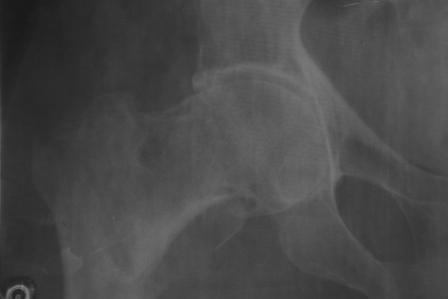

Чрезвертельный перелом бедра

Доставлена больная 72 года. 3 дня назад упала. На R-грамме чрезвертельный простой АО 31А1 перелом левой бедренной кости.

Кроме того имеется подозрение на субкапитальный 31В1 перелом , у меня на практике такое впервые. Трижды сделали R-графию, но качественный снимок не получилось. КТ в диагностическом центре на ремонте.

1. Действительно, имеется ли субкапитальный перелом, или мне так кажется?

2. Если да, то что можно делать? В наличии имеется длинные спонгиозные винты, большие расширяюшиеся в конце винты ЦИТО, Г- образные и продольные пластины АО, пластина Троценко-Нуждина, и мыщелковые пластины, заимствованные у Джолдаса. С уважением Абдурашид.